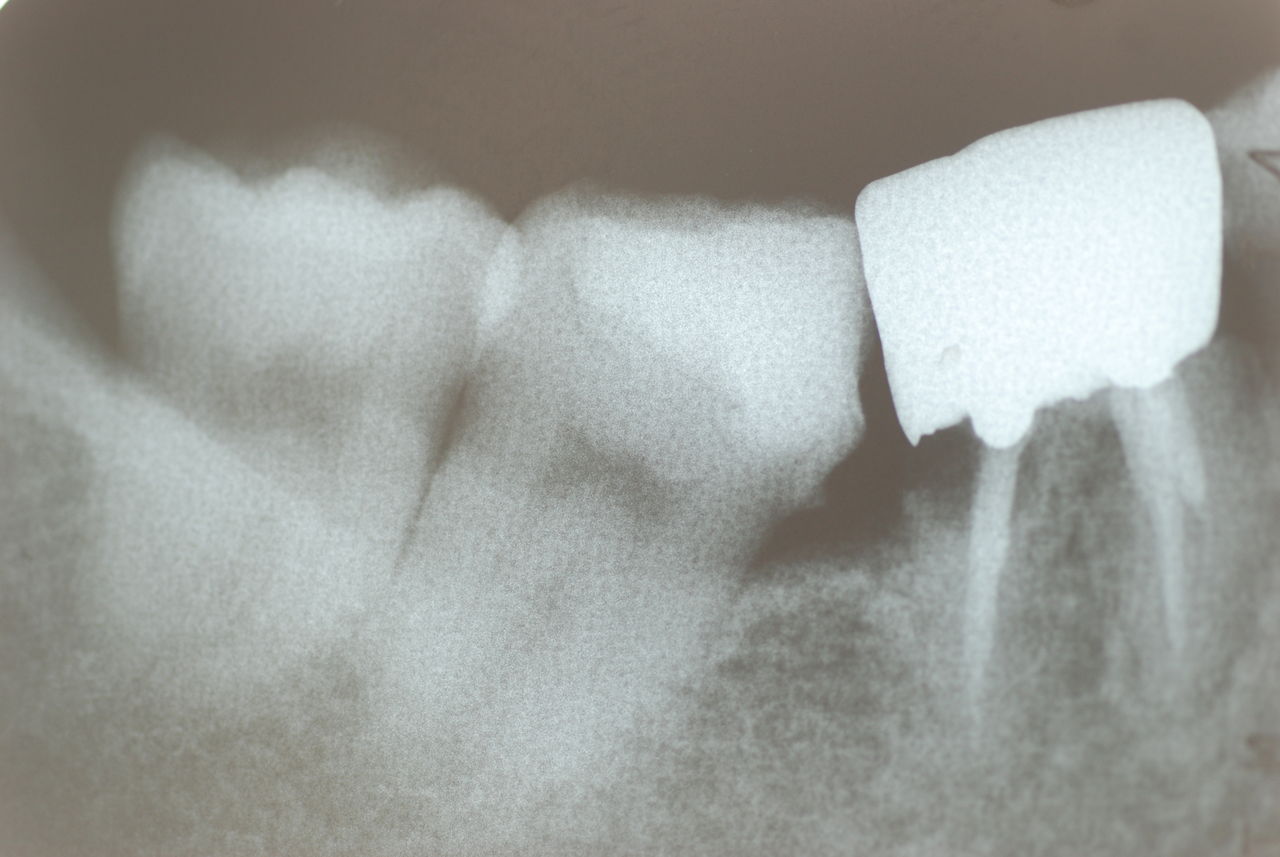

左下の歯は歯の中の治療も?ですごい歯周病を患い歯茎の穴(ポケットと呼ばれるところ)から膿が出ているのです。ばい菌と毒素で骨が溶けて深い穴ができてそこにまたバイキンと毒素がたまるという悪循環ができているのですね。

右下の歯は歯の中の治療もあやしいのですが、金属と歯の間がすでに虫歯で崩壊し始めています。

プラークというバイキンと毒素と食べかすの塊が歯の周りや歯茎にまとわりついて虫歯になり且つ重症の歯周病を患っています。